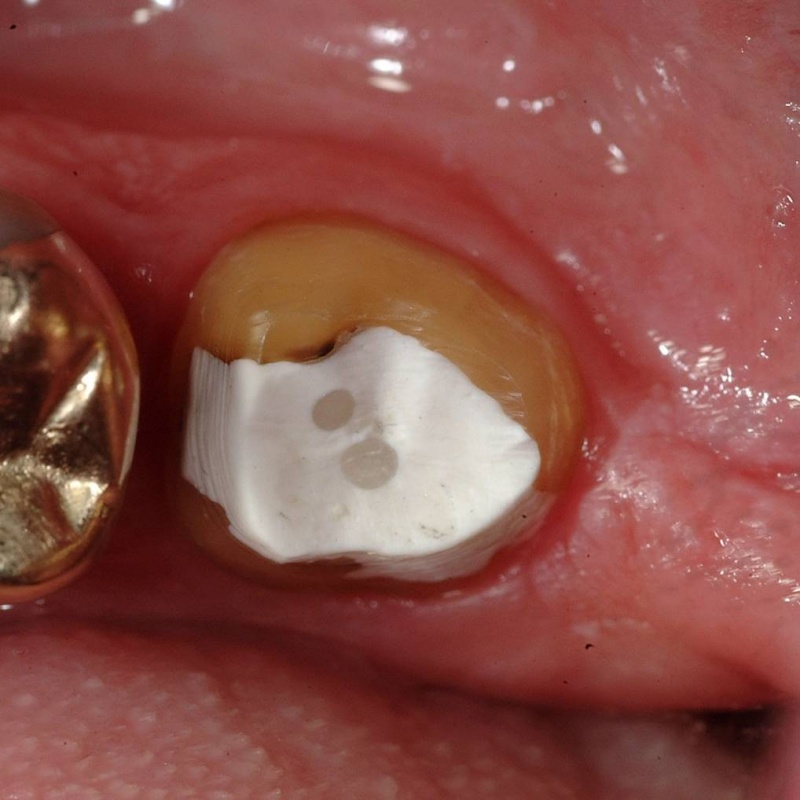

- Place Build-Up Material & Cure

- Sealing Occlusal Access Hole